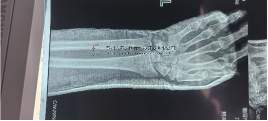

本病例由團(tuán)隊(duì)王書元主任主刀:股骨頸骨折術(shù)前X片術(shù)中三臂機(jī)器人復(fù)位六軸機(jī)器人輔助經(jīng)皮空心釘術(shù)中術(shù)后透視術(shù)后傷口圖人員照片圖本···

成永忠數(shù)智接骨團(tuán)隊(duì)開發(fā)脛骨干骨折X線影像 AI識(shí)別系統(tǒng)可快速通過脛骨干骨折X線正側(cè)位片識(shí)別脛骨干骨折三維模型,并出具包含骨折端···